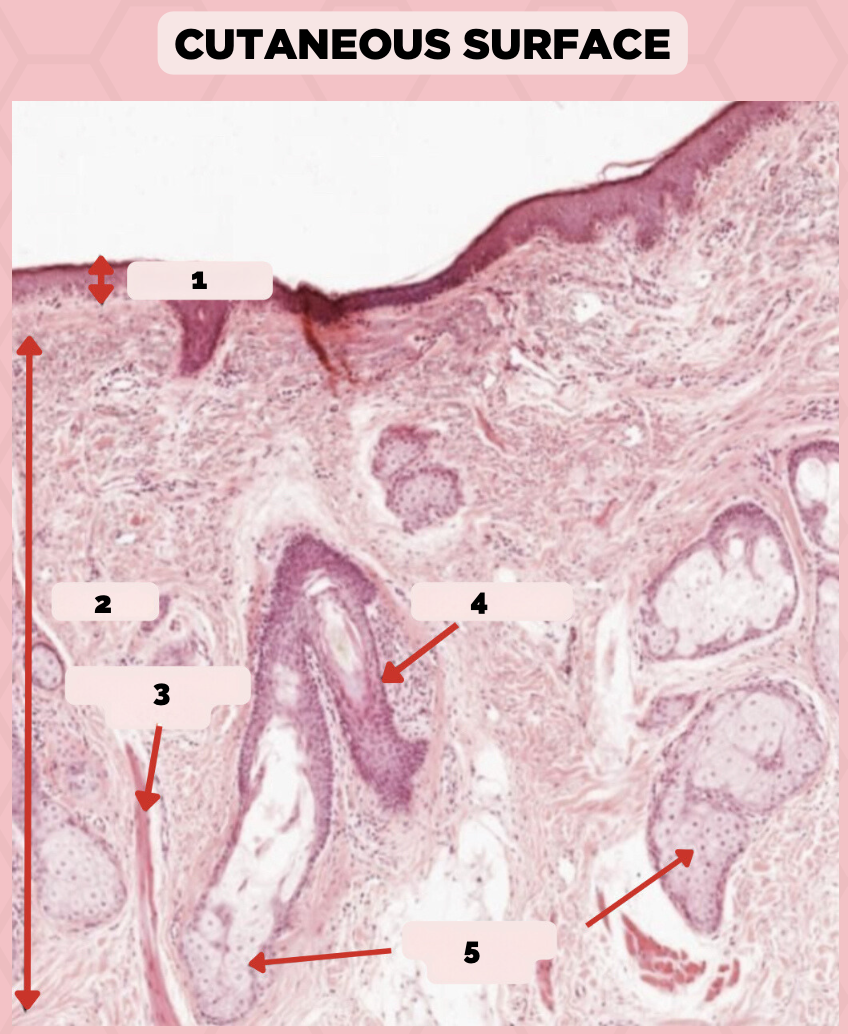

Lip

What is the specimen showed in the picture?

Epidermis

Identify the structure labeled as 1.

Dermis

Identify the structure labeled as 2.

Arrector Pilli Muscle

Identify the structure labeled as 3.

Hair Follicle

Identify the structure labeled as 4.

Sebaceous Glands

Identify the structure labeled as 5.